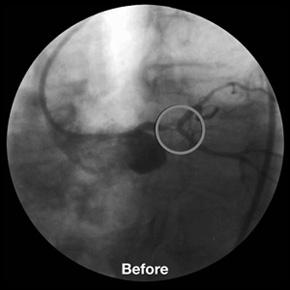

LMCA Y-Stenting with 3 BioDiamond stents.

9 x 3.5 mm distal LMCA,

9 x 3.0 mm ostial LAD and

9 x 3.0 mm ostial Cx.

CHP Beauregard, Marseille